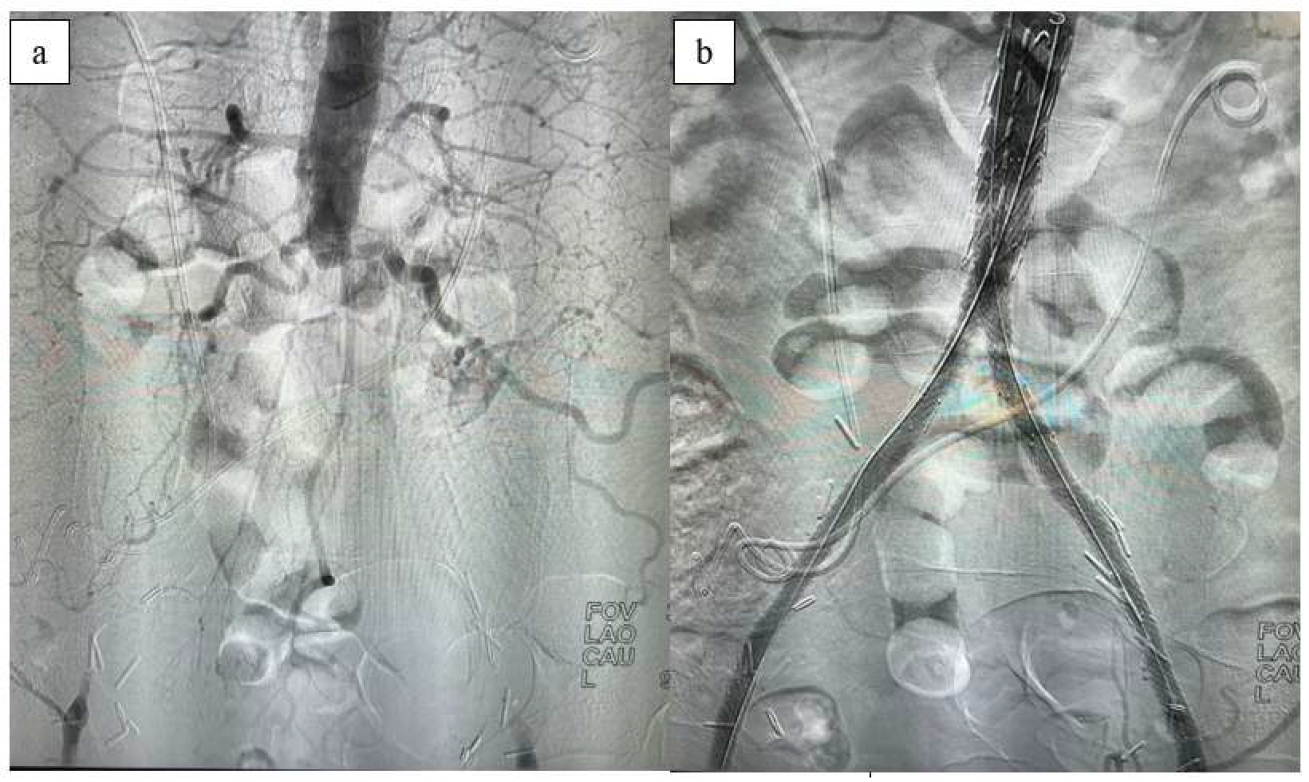

Two cases of arterial rupture and subsequent massive hemorrhage were managed during the procedure with intravenous transfusion and covered stenting. Post-procedure, there was a significant improvement in the ABI, which correlated with the Rutherford classification. The mean ABI, measured bilaterally, significantly improved from approximately 0.5 before the procedure to above 0.8 both immediately after the procedure and throughout the 2-year follow-up period. The one-way ANOVA (repeated measures ANOVA) test result shows an F-statistic of 0.42 and a p-value of 0.53. This indicates that there is no statistically significant difference between the mean values for the left and right sides across the different time points (pre-op, post-op, 3 months, etc.) in our dataset for the ABI measurement results from the follow-up assessments. The p-value is much higher than the typical significance level (e.g., 0.05), meaning we fail to reject the null hypothesis and conclude that the differences observed are likely due to random variation (Figure 3).

Figure 3. Preoperative and postoperative ABI measurements.